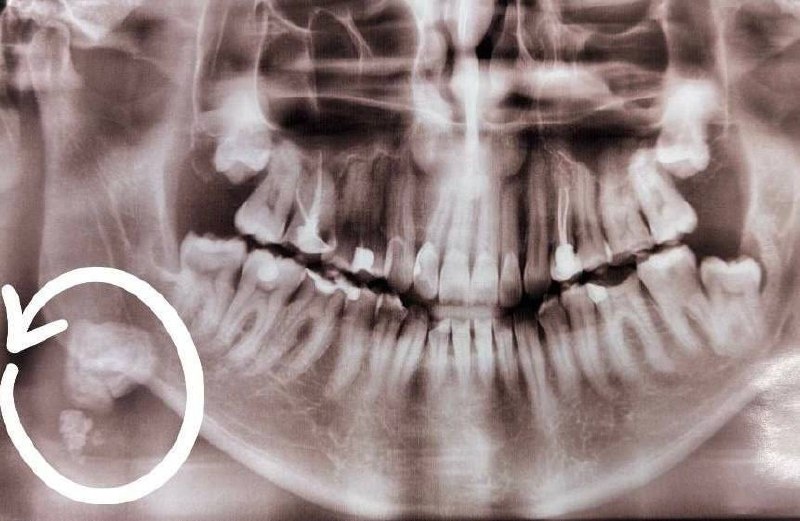

У жителя Омска удалили зубной камень размером с монету

У жителя Омска удалили зубной камень размером с монету 🦷

Во время профилактического осмотра в стоматологической поликлинике на Левобережье врачи обнаружили у пациента крупное образование в слюнной железе под нижней челюстью.

Как выяснилось, камень начал формироваться около 10 лет назад после травмы. Всё это время мужчина ощущал дискомфорт в области шеи, но к специалистам не обращался.

Образование пришлось удалять хирургически: самый крупный фрагмент достигал примерно 2 см в диаметре — как 1-рублёвая монета. Ещё два меньших фрагмента вышли позже самостоятельно.